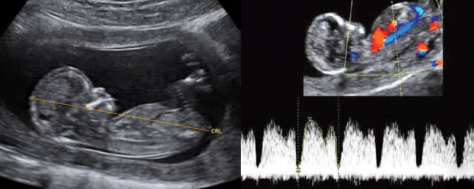

Ультразвукове дослідження підтверджує розвиток та визначає розміри плоду, з встановленням найбільш точного гестаційного віку плоду та дати пологів.

При скануванні ретельно оцінюються всі органі та системи: головний мозок, спинний мозок, обличчя, кістки, легені, діафрагма, серце, нирки, сечовий міхур, шлунок, кишечник, стінку живота, щоб діагностувати або виключити вроджені вади органів. Дослідження проводиться за допомогою кольорового та спектрального доплера, включно з ехокардіографією плода (УЗД серця плода).

При цьому також вимірюють розміри плоду та визначають його гестаційний вік і розвиток, оцінюють локалізацію, товщину та структуру плаценти, визначають кількость навколоплідної рідини, оцінюють довжину шийки матки. Дослідження триває 45 хвилин.